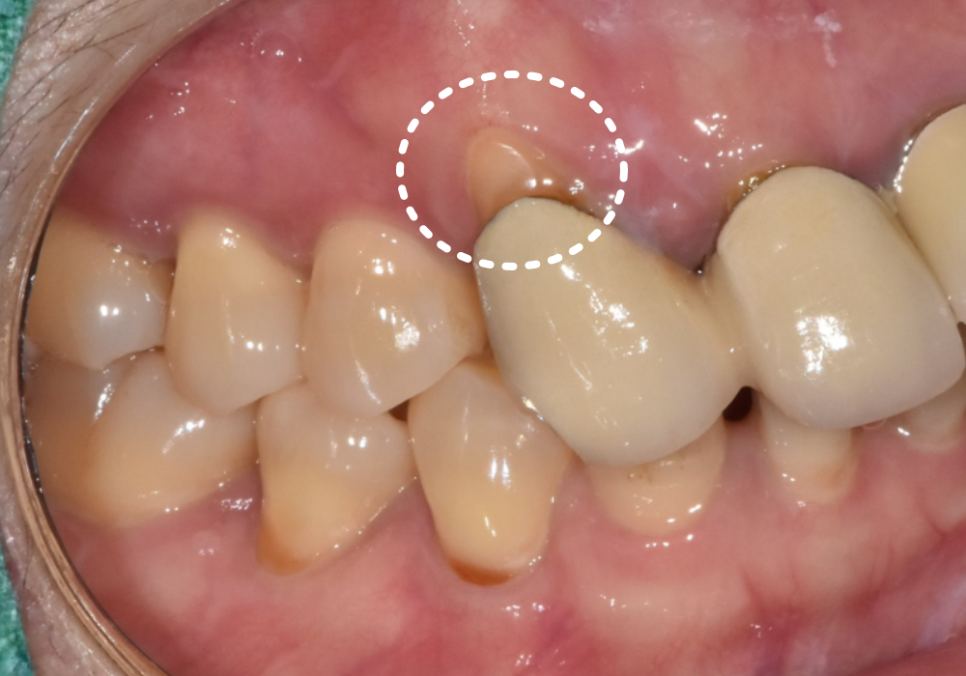

잇몸이 내려가면서

뿌리가 드러나보이고,

보철 안쪽의 금속 테두리가

까맣게 보였습니다.

무엇보다 "씹을 때 욱신거린다"는

통증을 호소하셨는데,

정밀 검사 결과 ,

과거 신경치료가 제대로 마무리되지 않아

내부에 염증이 생겨 있었습니다.

230215

결국 기존 재료를 모두 제거하고

다시 치료하는 '재신경치료'가

시급한 상황이었습니다.

230424

이번 환자분 역시 신경이

뿌리 끝까지 제거되지 않은 상태였지만,

다행히 숨은 길을 잘 찾아내어

3번의 꼼꼼한 소독 끝에

안전하게 치료를 마무리할 수 있었습니다.